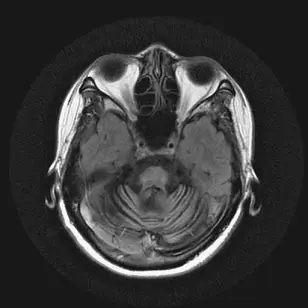

59歲男性因為姿勢性低血壓暈倒多次,他同時還有動作遲緩、步態不穩及性功能障礙問題,他的腦部磁振造影掃描結果如下圖,下列何者為最可能的診斷?

本題聚焦於多重系統萎縮症(multiple system atrophy,MSA)的典型臨床表現與影像學特徵:以自律神經功能衰竭(姿勢性低血壓、性功能障礙)、錐體下與錐體外症狀(動作遲緩、步態不穩)以及小腦與腦幹退化所導致的步態失調為關鍵,並輔以腦部MRI上「十字包子征」(hot cross bun sign)作診斷指標。

從橫斷面T2加權影像可見:

- 橋腦中央出現明顯的十字形高訊號帶,代表橫向的橋小腦纖維選擇性退化,加上縱向皮質脊髓束保存,形成典型「十字包子征」。

- 小腦及橋腦體積具不同比例萎縮,伴隨中線結構變窄。

此影像所示的「十字包子征」最具指向MSA-C(cerebellar variant)的特徵性意義。